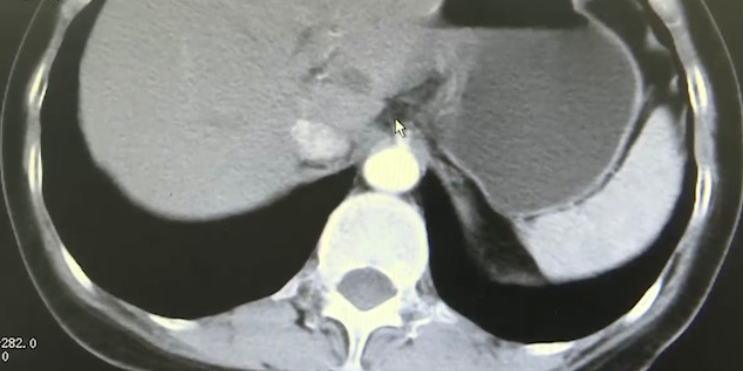

▲检查结果 。

根据媒体的报道 , 张女是一名资深的小学教师 , 平时工作认真负责的她经常三餐不准时 , 半年前开始出现胃部胀痛的感觉 , 由于多年来饮食不规律 , 肠胃一直不太好 , 便自行服药了一段时间 , 并没有在意 , 直到症状越来越严重 , 吃药也不见好转 , 这才前往医院检查 , 结果发现一部分胃已经「跑向」胸腔 , 被确诊为食管裂孔疝 , 需要进行手术治疗 。

医生随后为其安排了微创手术治疗 , 目前患者病情好转 , 已康复出院 。 医生介绍 , 食管裂孔疝在临床上并不少见 , 主要是胃的一部分经横隔的食管裂孔进入到胸腔而形成的 , 常见表现为上腹部饱胀、疼痛等 , 人们常常会与普通胃炎混淆而耽误就医;提醒大家生活要规律 , 不要暴饮暴食 , 饮食要清淡少抽烟喝酒 。